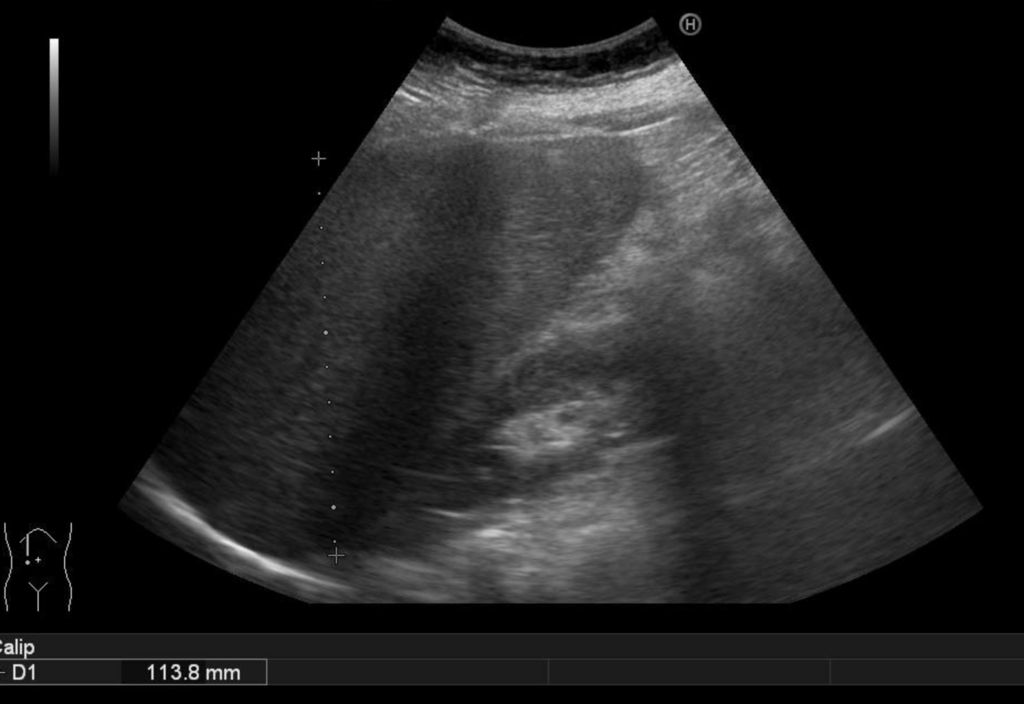

よくある測定法は肝臓右葉、左葉それぞれ縦断面(頭尾方向)で評価。

右葉は右乳頭線上の縦断像、左葉は大動脈に沿った縦断像で大きさを測定する。

(ただし左葉は一回で測定できるが、右葉は大きくて分割しないといけないのでつなぎ目もわからず正確な大きさの評価は難しいという意見もある。)